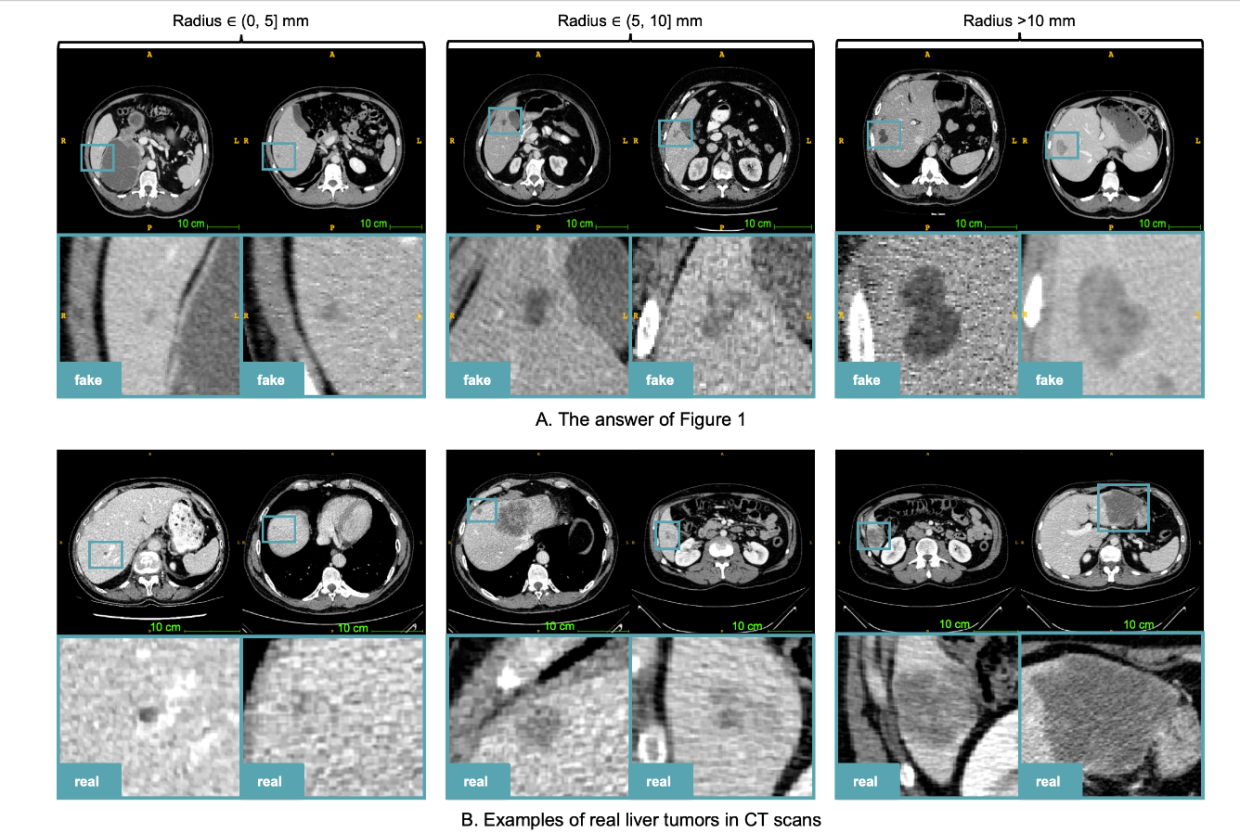

文章的实验中,专业的医生也难以区分生成的合成肿瘤图像与真实图像。此外,在合成肿瘤上训练的模型在分割真实肝脏肿瘤时获得了 59.81% 的 Dice 相似系数(Dice Similarity Coefficient,DSC),而只在真实肿瘤上训练过的模型获得了 57.63% 的DSC,这表明在训练时合成肿瘤有可能被用作真实肿瘤的替代品。

3.1 使用视觉图灵测试进行临床验证

作者对 50 次 CT 扫描进行了视觉图灵测试,其中 20 次扫描是 LiT 的真实肿瘤,其余 30 次扫描是 WORD 的健康肝脏和合成肿瘤。两位经验水平不同的专业人士参加了这次测试。他们可以在3D视图中检查每个样本。在测试中,专业人员可以将每个样本标记为真实的、合成的或不确定的。计算性能指标时,只计算具有确定结果的样本。

测试结果如下表所示: